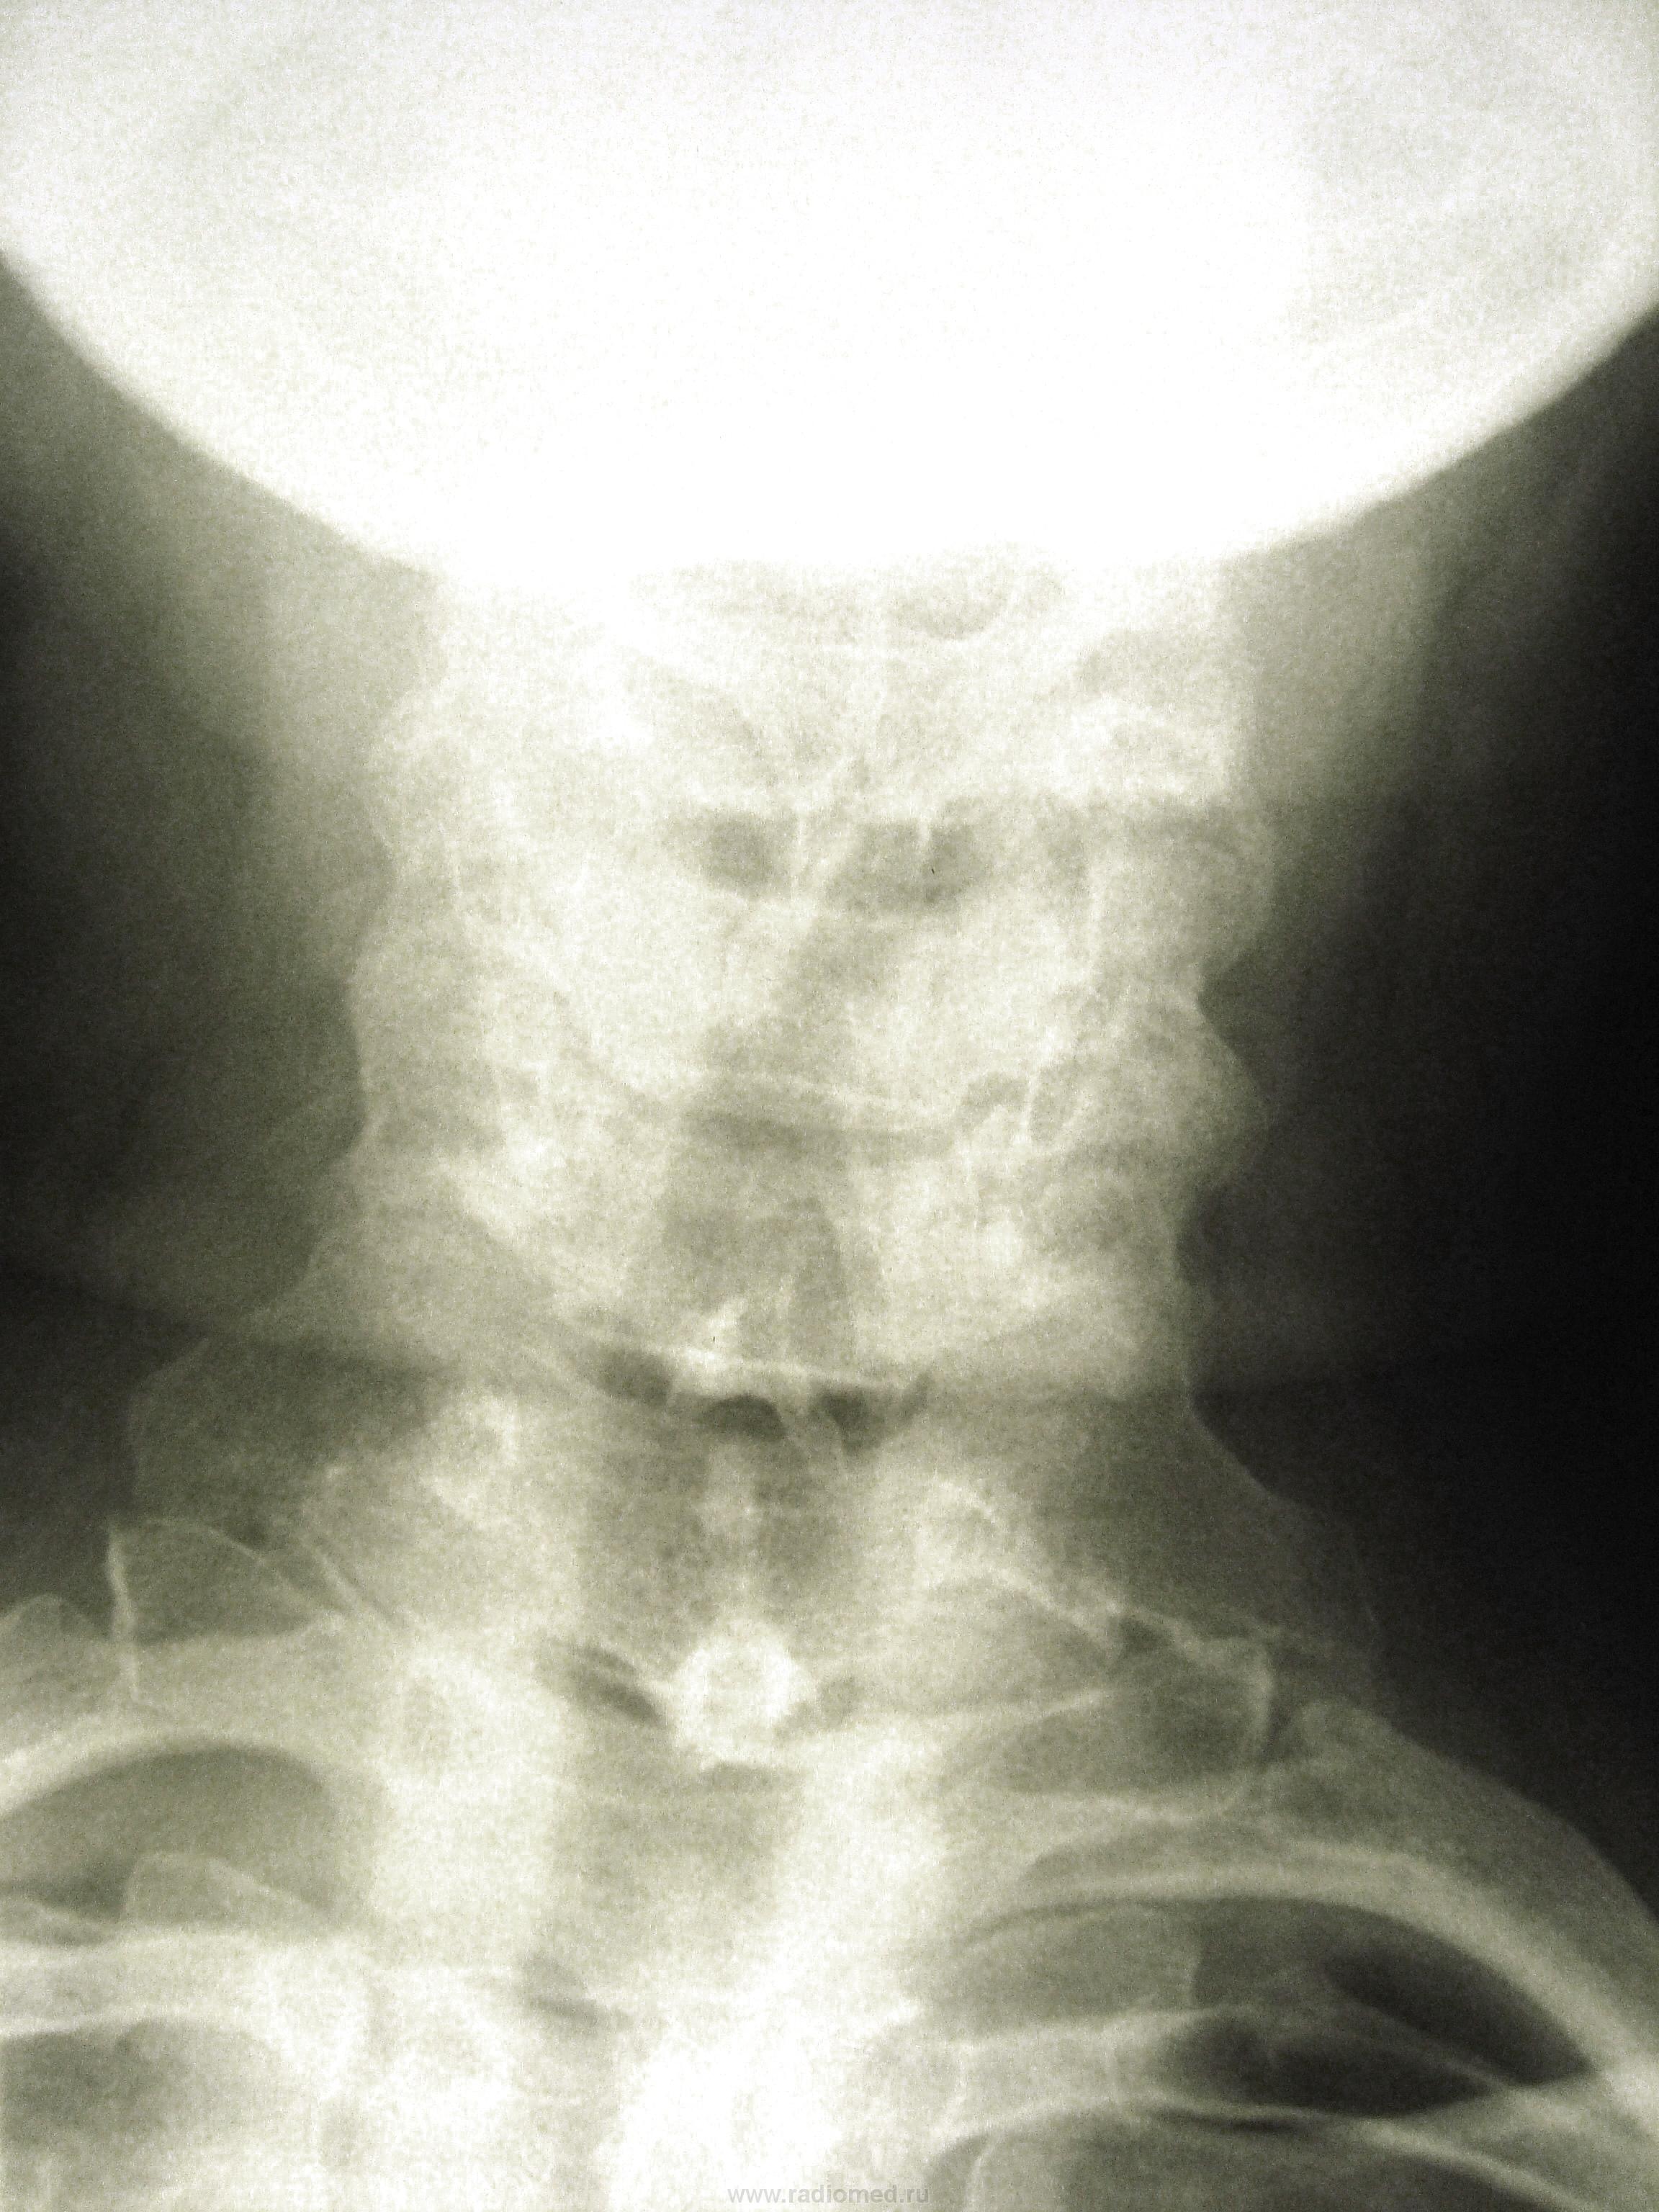

Гиперплазия шиловидного отростка височной кости. Гиперплазия шиловидного отростка височной кости известна довольно давно. В 50-е годы увеличенные шиловидные отростки активно оперировали отоларингологи. Клинически аномалия проявляется болями в горле при отсутствии воспалительных изменений. Считалось, что данная симптоматика обусловлена давлением увеличенного шиловидного отростка на стенку глотки и раздражением языкоглоточного нерва. Оба фактора приводятк дистрофическим изменениям в окружающих мягких тканях. Ф.А. Хабиров считает, что увеличенный шиловидный отросток височной кости способен быть причиной длительно прогрессирующего болевого синдрома в шейном отделе позвоночника. При рентгенографии на вертеброграммах шейного отдела позвоночника в 2-ух проекциях дифференцыруютсялинейные тени, соединяющие шиловидные отростки и малые рога подъязычной кости. Нередко данная аномалия сочетается с наличием костной перемычки задней дужки атланта-аномалией Киммерле. Неполноценность функции шейного отдела позвоночника приводит к раннему присоединению дистрофических изменений.

"На рентгенограмме краниовертебральной зоны в сагиттальной проекции продольная ось зуба аксиса составляет с продольной осью его тела угол, открытый кзади.

Иногда слияние зуба и тела 2 шейного позвонка происходит не по вертикальной оси, а под углом. В таком случае диагносцируют лордозированный аксис. Такое положение зуба изменяет распределение силовых нагрузок краниоцервикальной зоны и приводит к видимым сложностям при определении краниометрических показателей. З.Л. Бродская рекомендует при наличии этой аномалии в вычислениях проводить касательную к зубу С2."

"Аномалии величины, асиммтричное положение оси суставных отростков.

Довольно часто суставные отростки одного и того же позвонка имеют неодинаковые размеры. Внекоторых случаях можно диагностировать резкое уменьшение их размеров, что может свидетельствовать об их гипоплазии. И.Л. Тагер и В.А. Дьяченко считают: из-за того что гипопластичный сустав обладает большей подвижностью, в данном двигательном сегменте создаются условия для раннего развитияповреждения межпозвонкового диска- остеохондроза и, возможно, соскальзывания позвонка".

На мой взгляд, в последнем случае, аномалия тропизма - когда щель межпозвонкового сустава расположена не в сагиттальной плоскости, а во фронтальной.

Преобладающим (в т.ч. в клинике) будет асимметрия величины суставных отростков (гипоплазия левых двух) (И)

аномалия тропизма (но, поправлю, суставная щель НЕДАЛЕКО "ушла" от сагиттальной плоскости : до фронтальной далеко...)